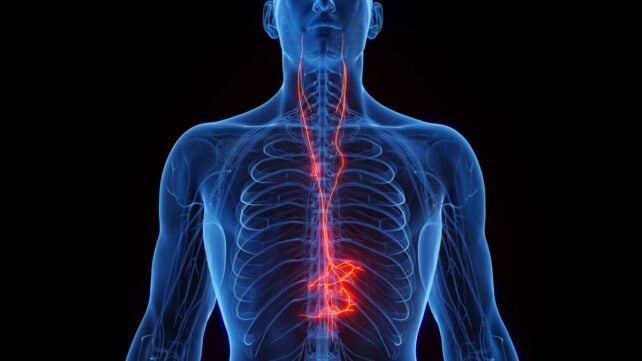

The vagus nerve carries information between the brain and organs in the chest and abdomen, such as the heart and intestines, helping the brain monitor and regulate many of the body's essential organs. It is responsible for sending rest and digest messages throughout the brain and body, stimulating digestion and promoting cellular repair.

Vagus nerve stimulation for epilepsy and depression generally involves implanting an electrical stimulator in the left side of a patient's chest, where the vagus nerve passes. Noninvasive devices for treating headaches deliver gentle pulses of electricity to certain places on the neck or ear where the vagus nerve is very close to the surface of the skin.